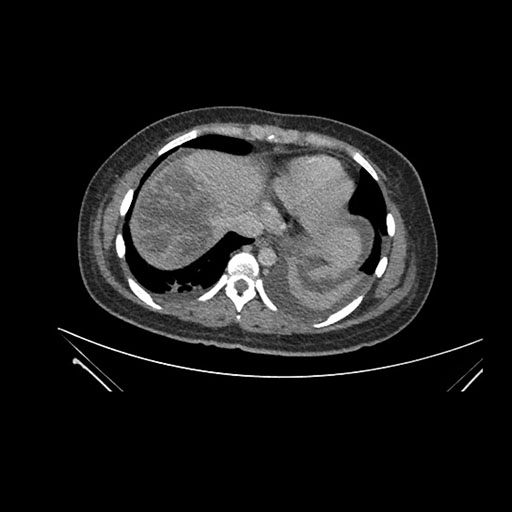

Imaging Analysis

Look through the patient's CT scan to identify any areas of concern for the necessary procedure.

Coronal Arterial